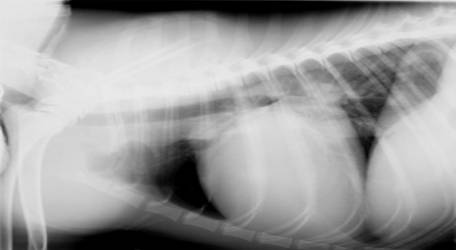

En la presentación, el gato está muy deprimido, prácticamente obtundido. La frecuencia respiratoria es de 50, con posibles movimientos abdominales paradójicos y esfuerzo claramente incrementado.

- Las membranas mucosas pálidas con un tiempo de rellenado capilar de más de dos segundos, y una frecuencia cardíaca de 200. Los sonidos cardíacos están muy amortiguados, así como los sonidos pulmonares ventralmente. Los sonidos pulmonares dorsales son normales.

- Lamentablemente, la máquina de ultrasonidos está siendo reparada, y un compañero está en rayos X con un perro anestesiado tomando múltiples tomas para una cirugía ortopédica.